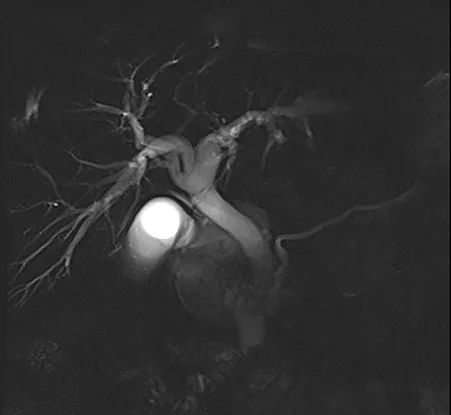

Le diagnostic positif de maladie de Caroli repose sur la cholangio-IRM. Celle-ci met en évidence de volumineuses dilatations kystiques des VBIH, en communication avec le reste de l’arbre biliaire (figure 7A). Il est fréquent de visualiser des calculs au sein des dilatations kystiques (figure 7B). Après injection de produit de contraste, il est classique de visualiser un vaisseau réhaussé (branche de la veine porte ou de l’artère hépatique) au sein de la dilatation kystique (figure 7C). Ce signe radiologique dit « central du point » (central dot sign), témoin d’une malformation de la plaque ductale, est pathognomique de la maladie de Caroli. Dans la maladie de Caroli isolée, les dilatations kystiques peuvent être localisées au niveau d’un lobe ou d’un segment hépatique, alors qu’elles sont généralement diffuses dans le cadre du syndrome de Caroli (tableau 1). Concernant le diagnostic de FHC, l’apport de l’imagerie est plus limité, mais permet d’évaluer la présence de signes radiologiques d’HTP (splénomégalie, voies de dérivations porto-systémiques). Il peut néanmoins exister des lésions biliaires associées à la FHC isolée sans syndrome de Caroli, à type de cholangite ou d’augmentation de volume de la vésicule biliaire (23).

Figure 7 : Visualisation par IRM hépatique de lésions caractéristiques de maladie de Caroli : dilatation kystiques (étoiles) des canaux biliaires intra-hépatiques (A) ; présence de calculs (flèches) au sein des dilatations kystiques biliaires (B) ; central dot sign : vaisseau réhaussé au sein d’une dilatation kystique (flèche) (C)